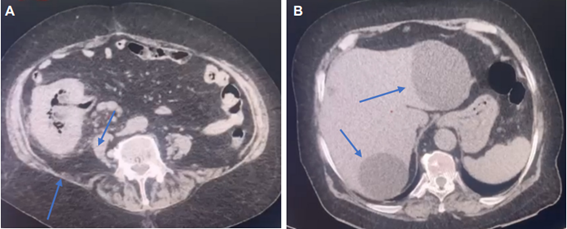

Paciente femenina de 85 años, con antecedente de hipertensión arterial sistémica, enfermedad pulmonar obstructiva crónica e insuficiencia cardiaca congestiva, quien acudió al área de urgencias del Hospital General de Chihuahua Salvador Zubirán Anchondo, en Chihuahua, México, por cuadro clínico de dolor abdominal localizado en fosa iliaca derecha, de 8 días de evolución, acompañado de náuseas, vómito y fiebre no cuantificada. En los paraclínicos había leucocitosis (25.400 mm³) con neutrofilia (93 %), hemoglobina 12,6 g/dL y plaquetas 388.000 u/mcL. En la tomografía de abdomen reportaron tiflitis, cambios inflamatorios periapendiculares, en grasa del íleon y ciego y aumento de tamaño de ganglios mesentéricos a nivel de fosa iliaca derecha (Figura 1).

En la valoración por el cirujano de turno en urgencias la encuentra desorientada, con palidez de mucosas y piel seca, estertores audibles en ambos campos pulmonares, disminución de la peristalsis y resistencia muscular abdominal, con signos de irritación peritoneal, además de signos apendiculares como McBurney, Psoas, Blumberg y Rovsing. Por sospecha de una apendicitis aguda complicada, se pasó a la sala de operaciones para su manejo definitivo.